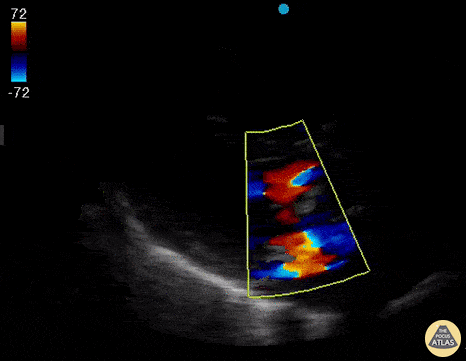

Parasternal long axis view in a patient with severe mitral regurgitation. Rohan Rastogi, MD @RohanRastogiMD